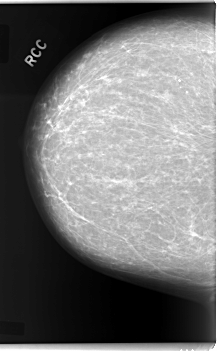

C_0084_1.RIGHT_CC

LEFT_CC LINES 5904 PIXELS_PER_LINE 3832 BITS_PER_PIXEL 12 RESOLUTION 50 OVERLAY

FILE: C_0084_1.LEFT_CC.OVERLAY

TOTAL_ABNORMALITIES 1

ABNORMALITY 1

LESION_TYPE MASS SHAPE LOBULATED MARGINS CIRCUMSCRIBED

ASSESSMENT 4

SUBTLETY 5

PATHOLOGY MALIGNANT

TOTAL_OUTLINES 1

BOUNDARY